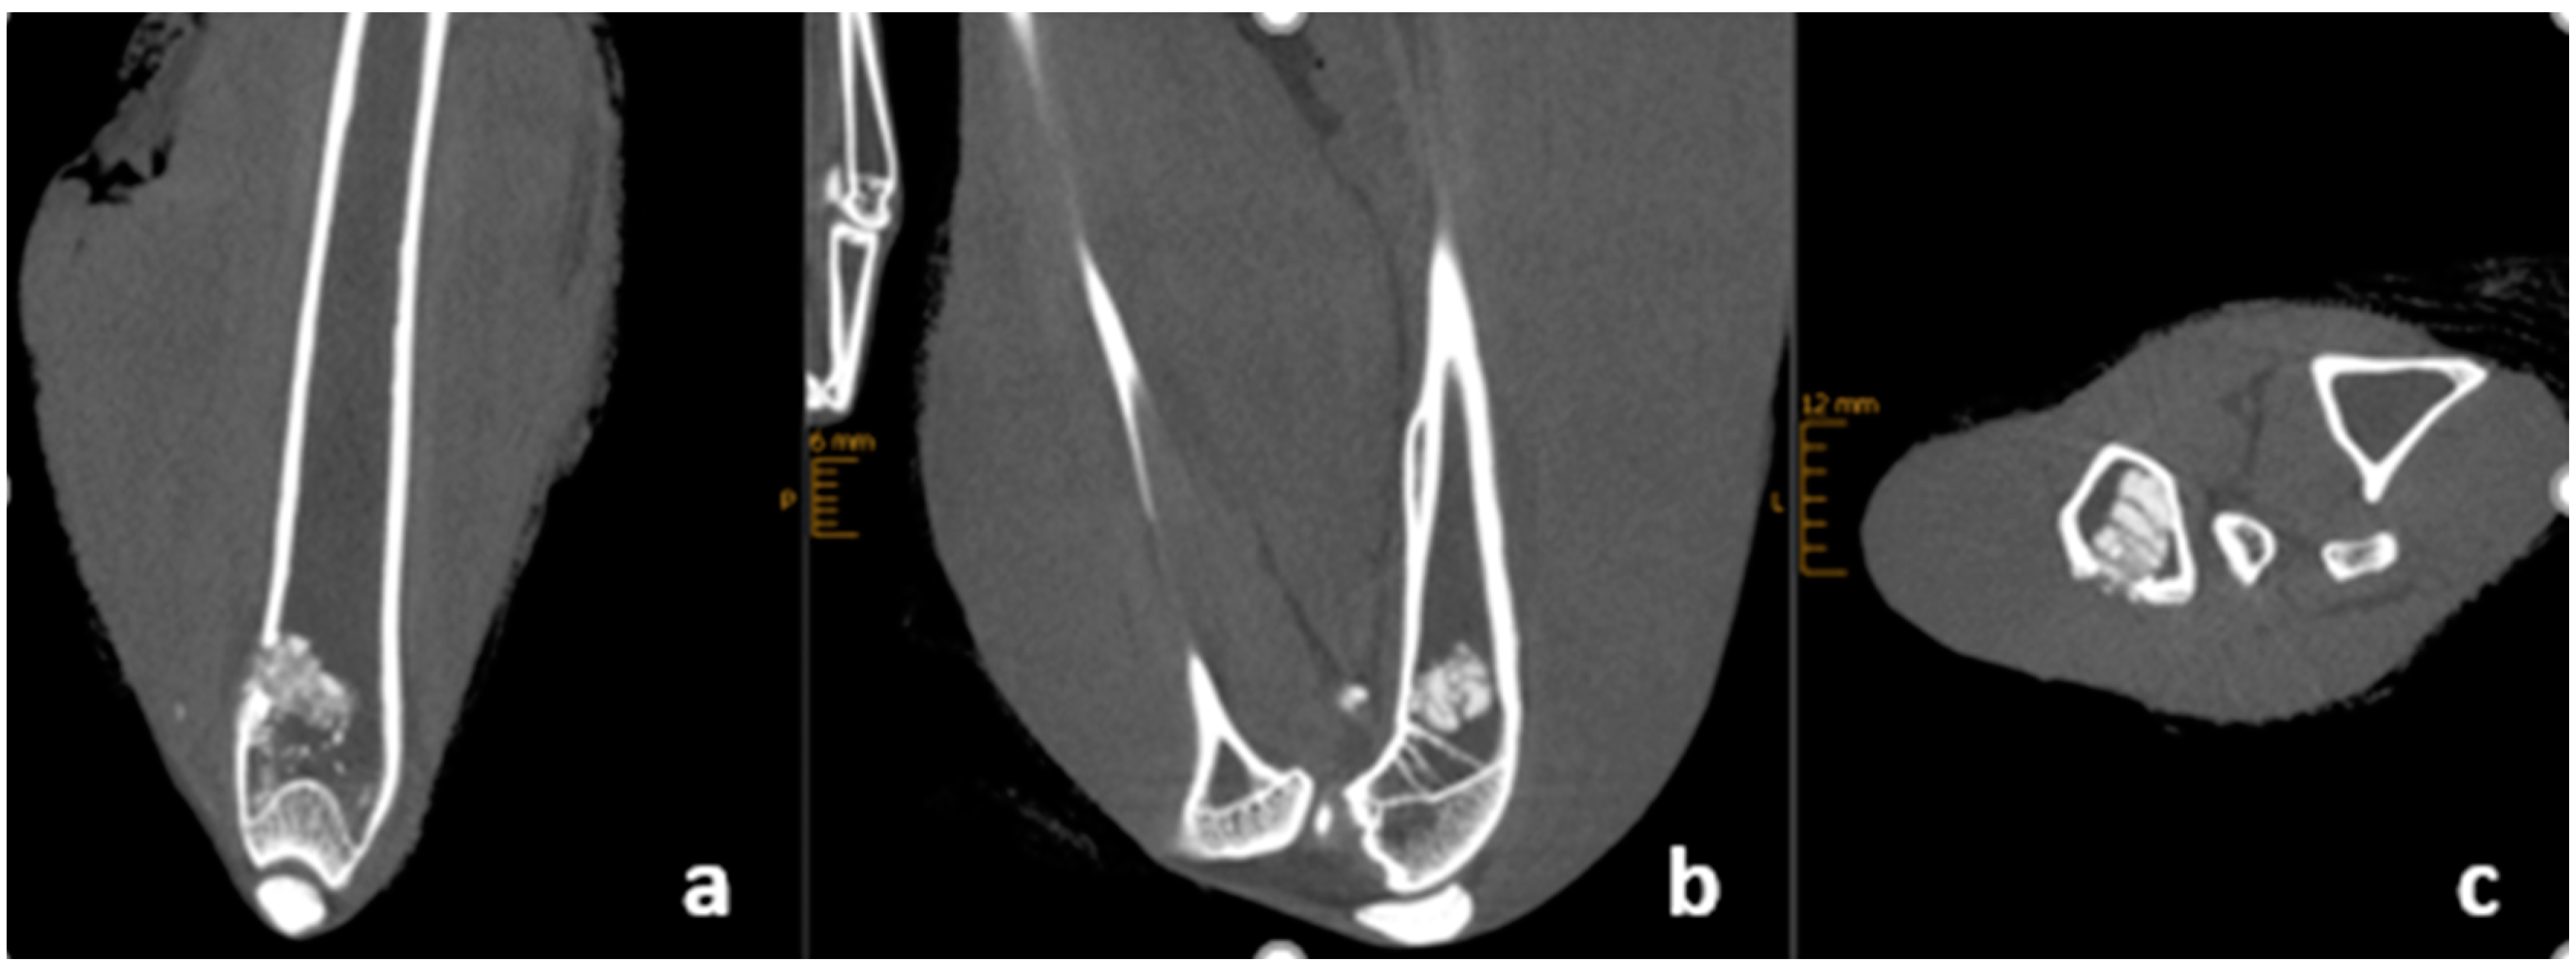

2.4. X-ray and CBCT Imaging

3.5. Radiological Outcome